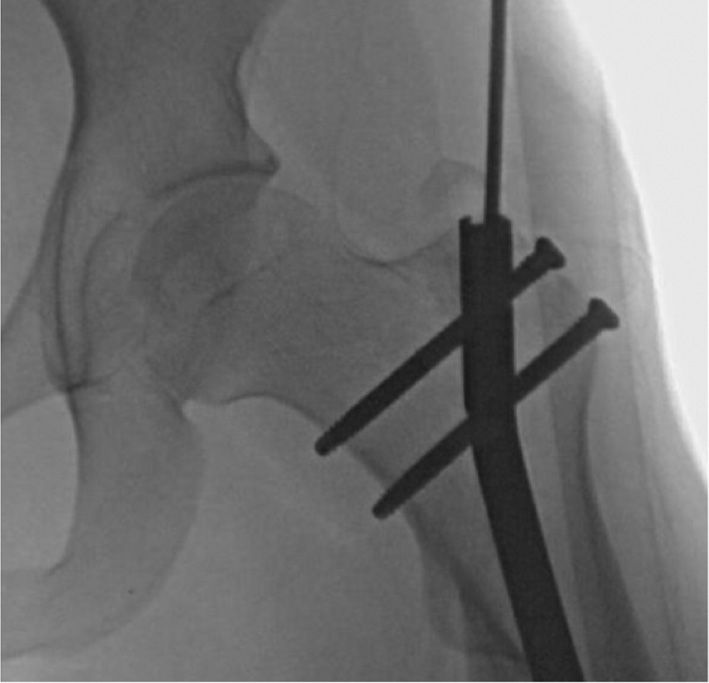

Figure 22. The exact position of the pegs/screws is localized by fluoroscope. The proximal screw/peg is removed percutaneously by dissecting through the fascia and muscle down to the screw head.

jposna20220031_fig22.jpg